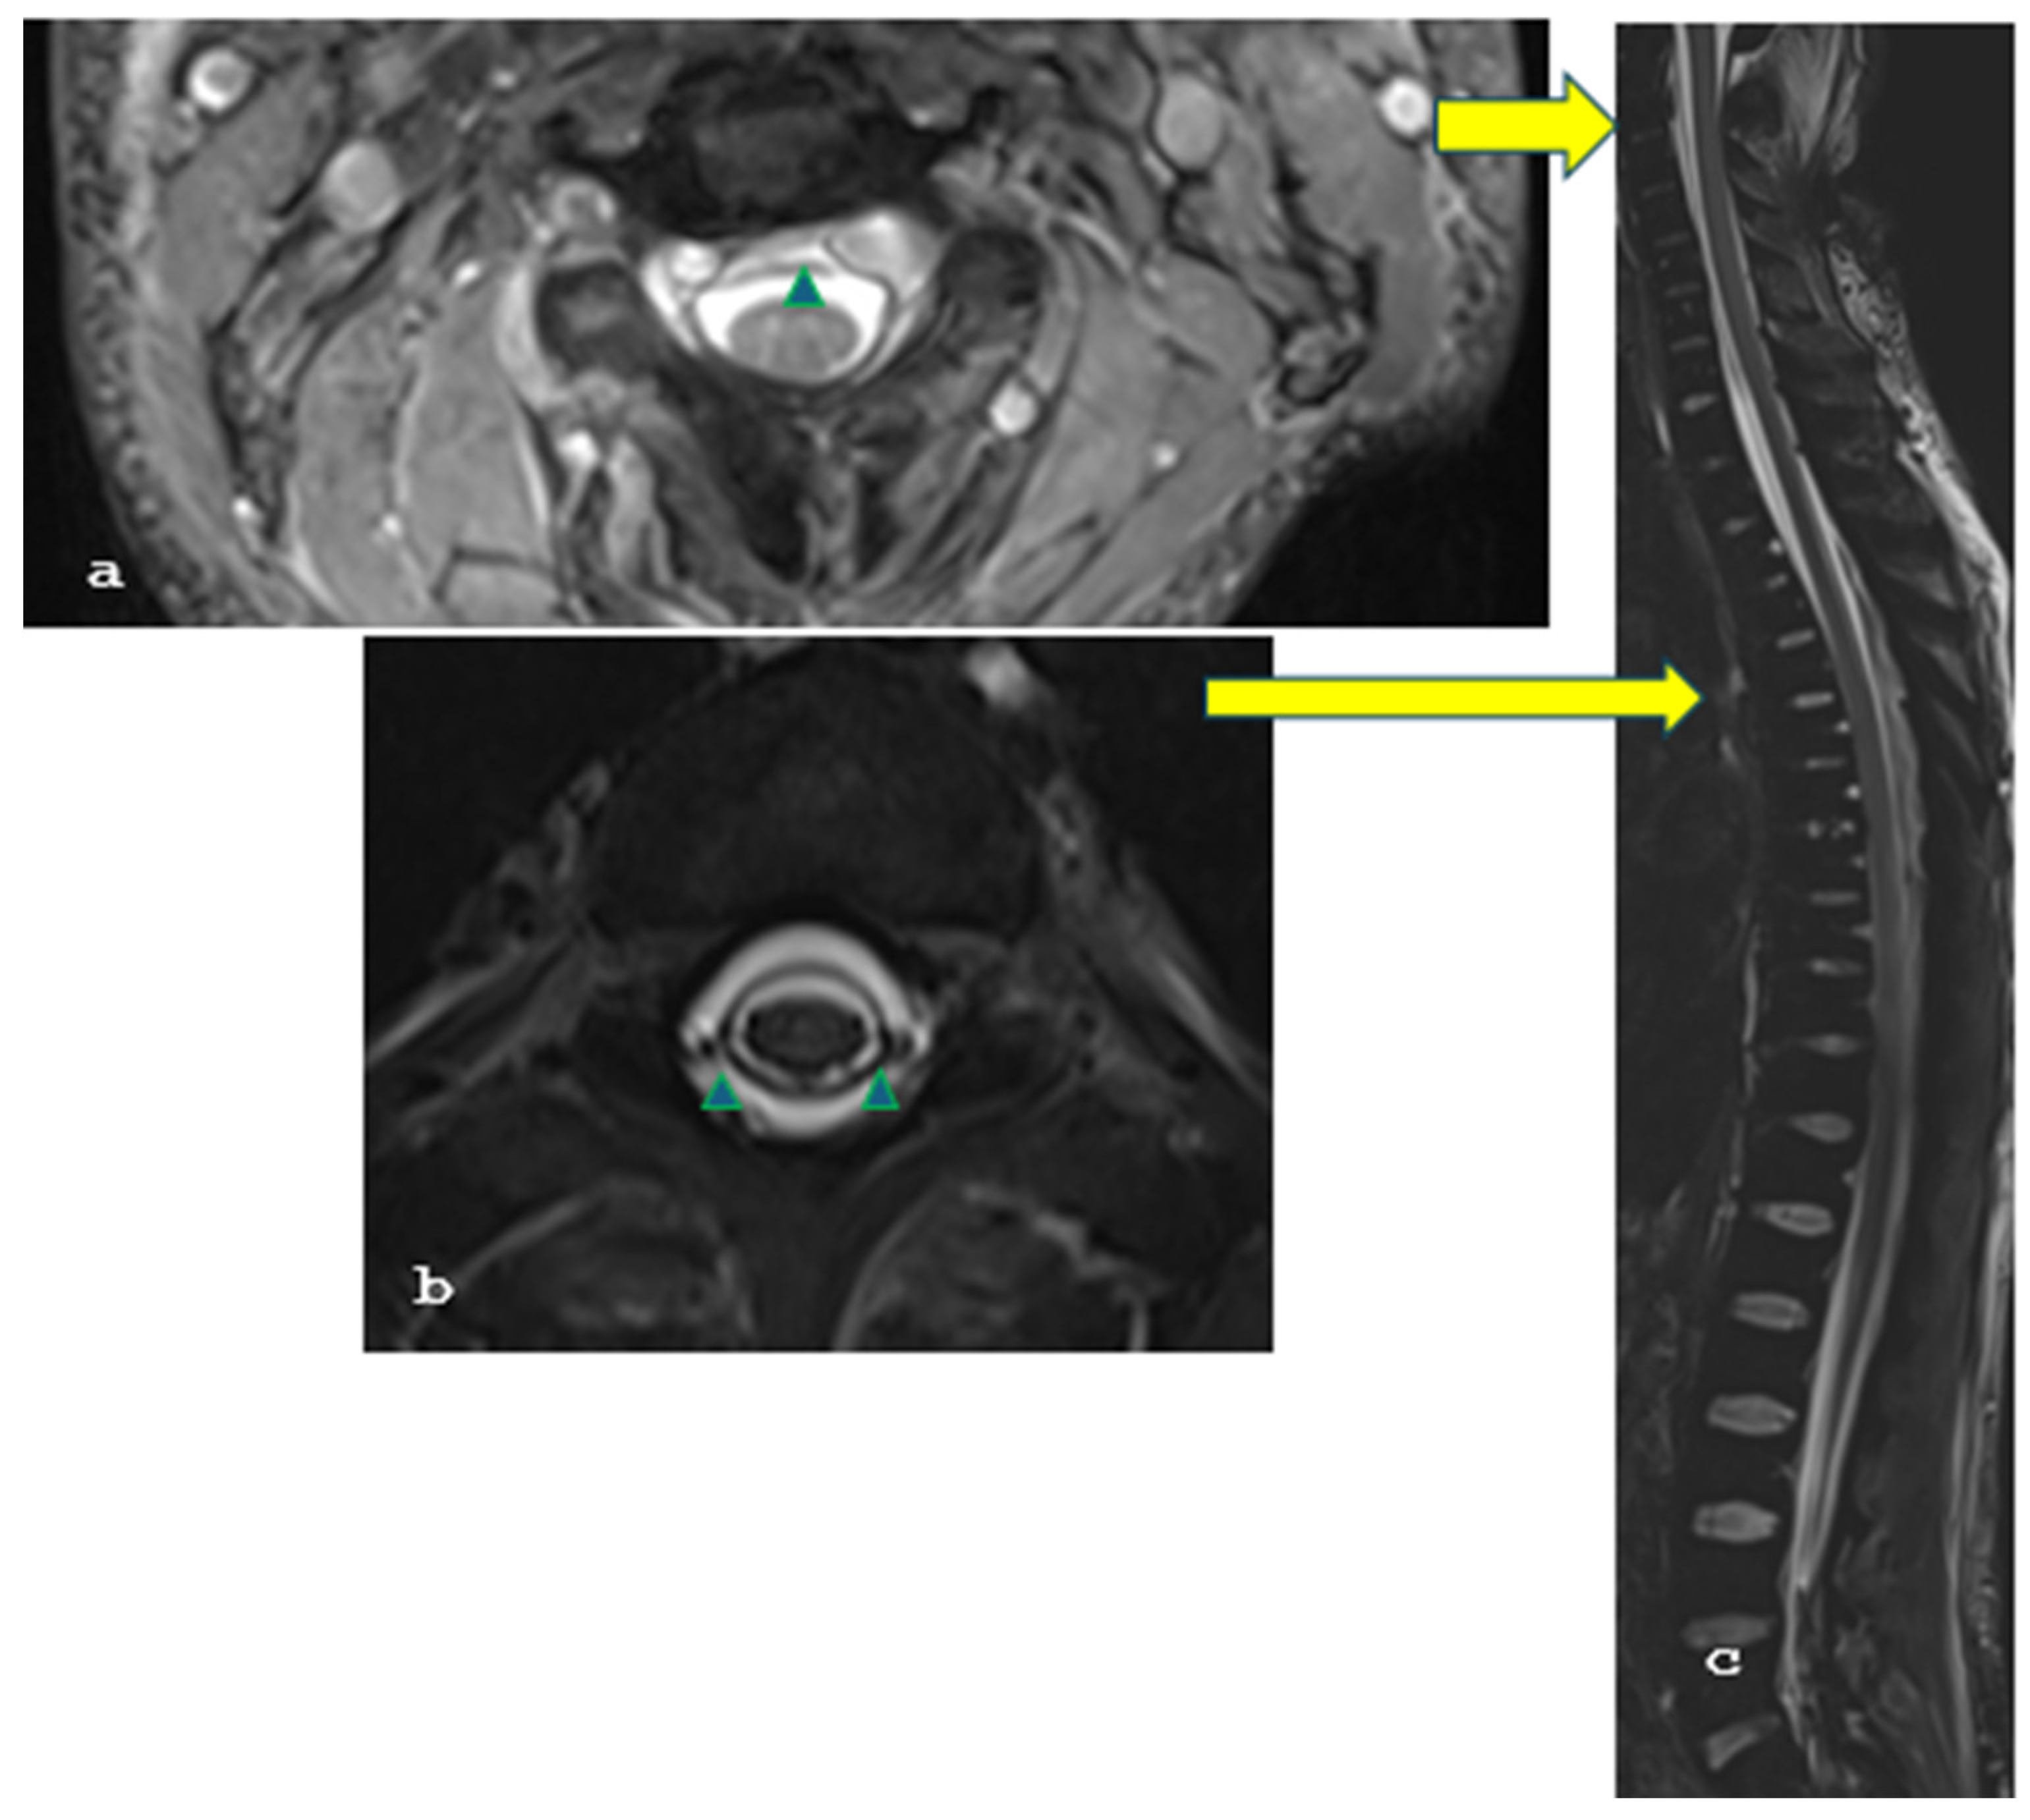

2. Case Report